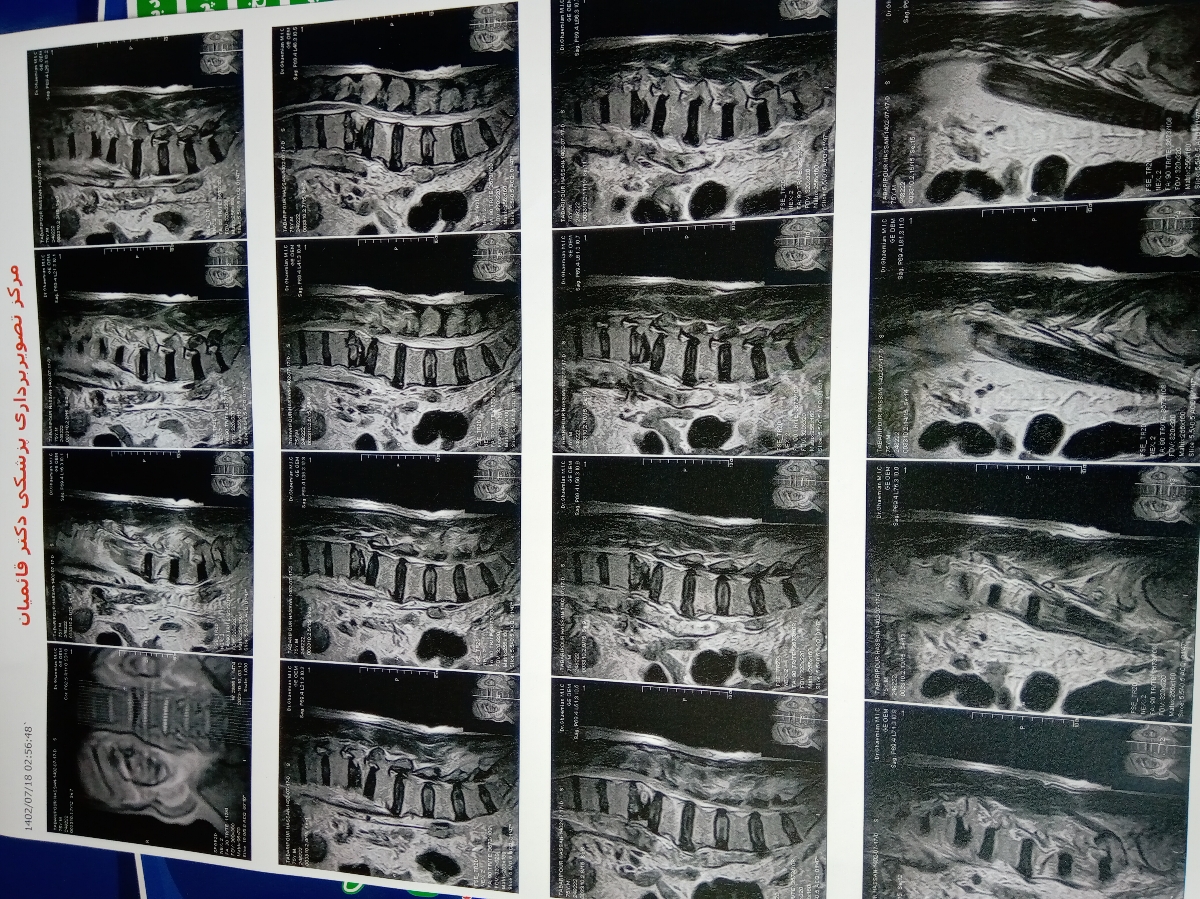

سلام دکتر جان این عکس ام ار ای فرستادم

میشه لطف کنین ببینین